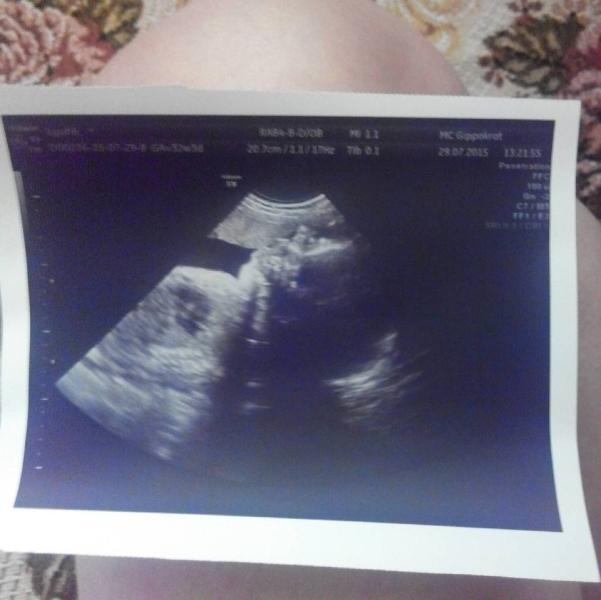

всем привет)ездила на последнее узи))ух))я так рада))сынок весит 2060.Активно толкал в меня своей ручкой и зевал))Доплер тоже отличный)хотя раньше было гиподинамические нарушения1б степени.Сейчас все ушло)))Блин я так рада)))

29.07.2015